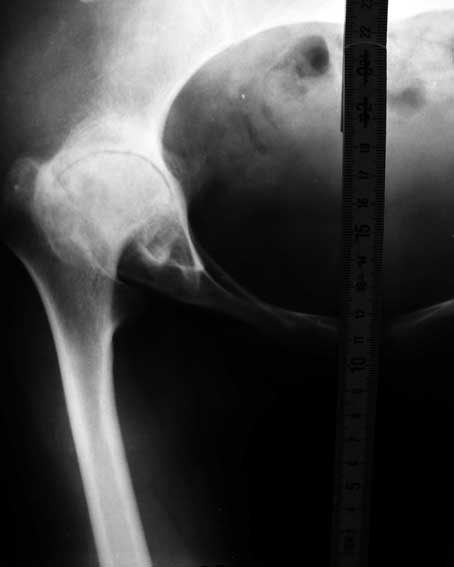

Уважаемые коллеги! Хотелось бы получить совет по тактике лечения. Обратилось 2 девушки - 25 и 26 лет. У обеих грубейшие сгибательные контрактуры тазобедренных суставов.

В одном случае после многократных операций в детстве по поводу врожденных вывихов бедер, в другом - ревматоидный полиартрит. Обе очень маленькие.

Перепробовал все имеющиеся виды шаблонов ножекпротезов - не подходят. На картинке линейка как масштаб - ширина 15мм.